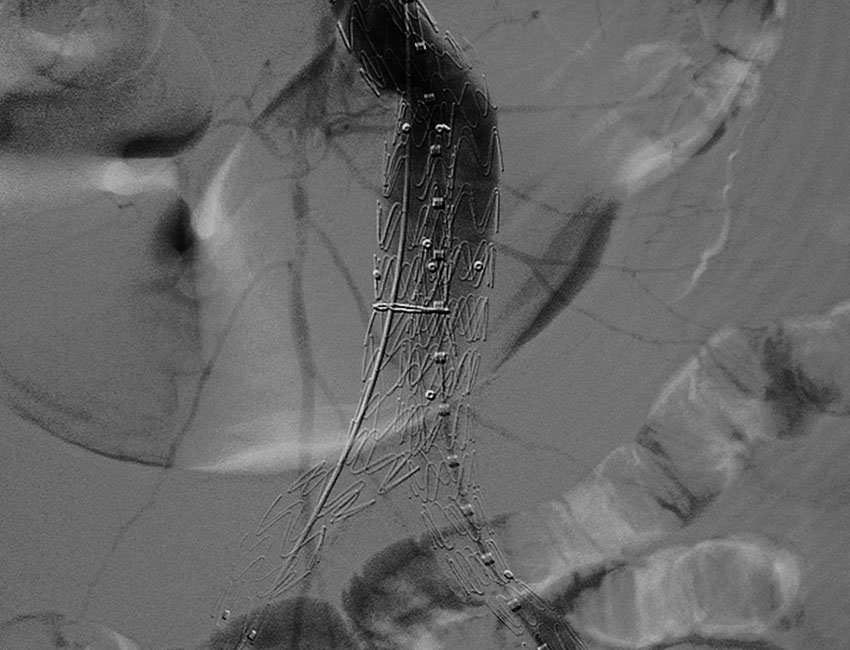

• Η διαδικασία: Μέσω δύο μικρών τομών στις βουβωνικές χώρες, ο αγγειοχειρουργός εισάγει έναν ειδικό ενδονάρθηκα (stent-graft) στην αορτή υπό ακτινοσκοπική καθοδήγηση. Το μόσχευμα αποκλείει το ανεύρυσμα από την κυκλοφορία, δημιουργώντας έναν νέο αυλό για το αίμα.

• Περιορισμοί: Απαιτεί ισόβια παρακολούθηση με αξονικές αγγειογραφίες ή υπερήχους για τον έλεγχο πιθανών μετακινήσεων ή διαρροών (endoleaks).